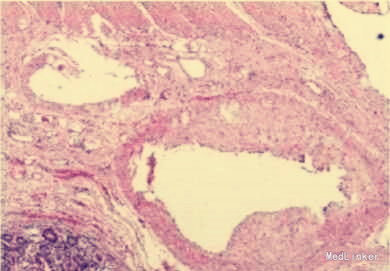

诊断:1.低血容量性休克;2.腹痛伴黑便查因;3.门静脉高压? 治疗:在积极抗休克的同时,决定行剖腹探查术。术中,胃食管下段区域及腹膜后曲张静脉丛未见出血,一段小肠与腹壁形成粘连,粘连处有一支发自肠系膜的曲张静脉穿经小肠,再进入腹壁。该段肠腔中充满淤血,其近端肠腔未发现血液,而远端集聚大量血液。术中肠镜检查发现胃至小肠末端区域血管扩张,但均无出血,小肠与腹壁粘连处曲张静脉有出血点。在结扎曲张静脉、切除出血肠段后,患者血压快速回升。

门静脉高压所致静脉曲张常发生在食管下段、胃部或直肠,极少数可发生在消化道其他位置。消化道外异位曲张静脉则非常罕见。1项纳入169例异位曲张静脉出血的研究显示,17%的异位曲张静脉位于十二指肠,17%位于空、回肠,14%位于结肠,8%位于直肠,9%位于腹膜。对于腹痛黑便的患者患者要小心门静脉高压的可能,尽早针对性治疗。